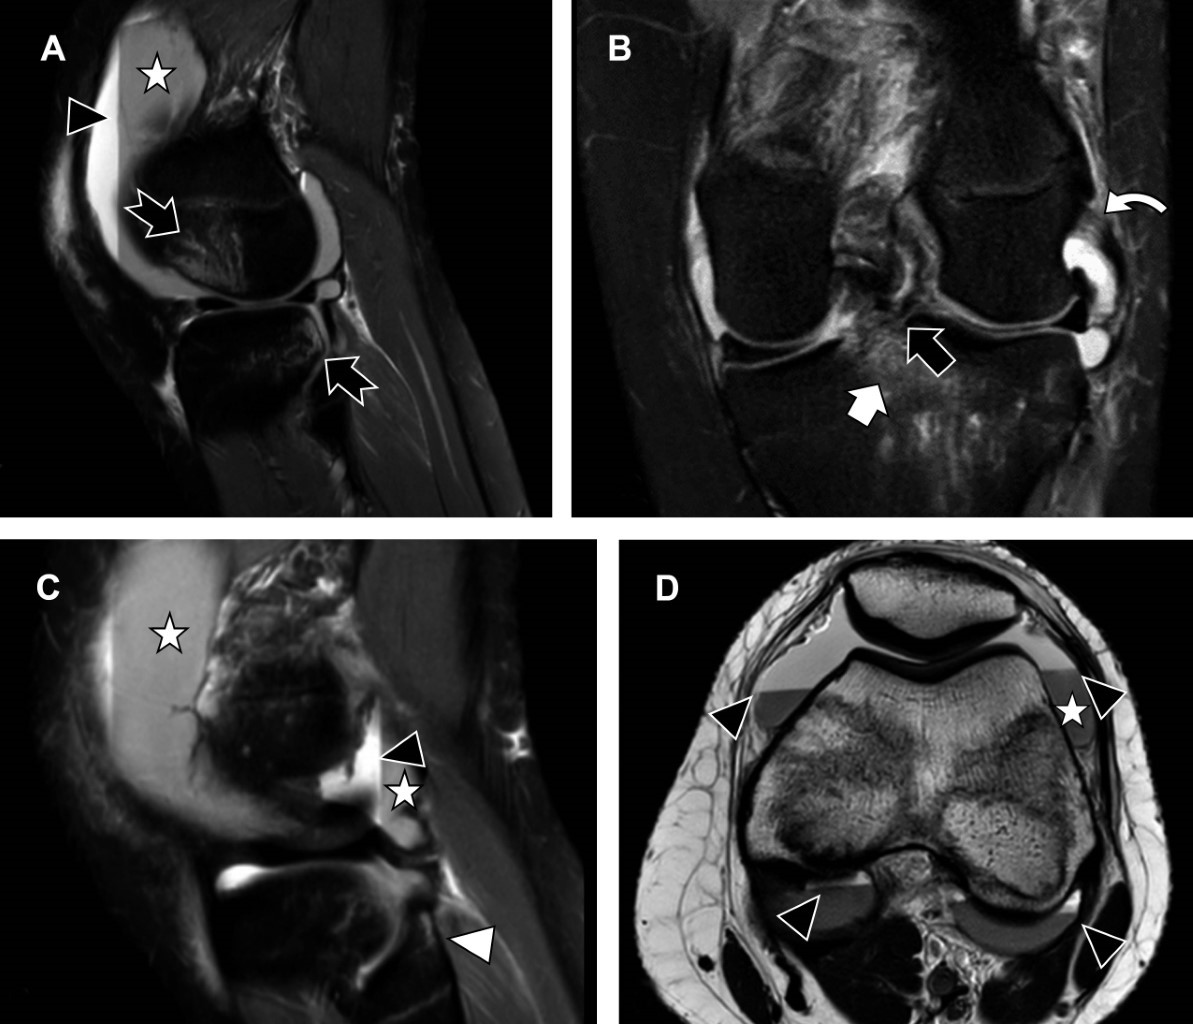

Femenino de 15 años que acude para la realización de RM de rodilla izquierda por sospecha de lesión del LCA. El mecanismo de lesión fue estrés en valgo forzado por contacto, mientras practicaba fútbol. La RM demuestra una fractura avulsión unifragmentaria del LCA, con medidas en el plano sagital de 1.3 cm en su eje anteroposterior por 6.5 mm de grosor, con una separación de su borde anterior de 6 mm, lo que indica una fractura por avulsión tipo II según la clasificación de Meyers y McKeever (Figura 1). Entre las lesiones concomitantes se encuentran una lesión grado II del ligamento colateral lateral (LCL), lesión grado II del ligamento peroneopoplíteo, hemartrosis, así como edema de la médula ósea, característico de pivot shift (Figura 2).

Las lesiones concomitantes asociadas incluyen: edema de la médula ósea en 92-93%, lesión del menisco medial en 54-60%, lesión del menisco lateral en 15-33%, lesión del ligamento colateral medial en 15-17%, lesión el cartílago en 12-14%, lesión del LCL en 2-2.6% y fractura de Segond en 7-12%.3 La afectación de la esquina posterolateral es infrecuente, al ser estructuras estabilizadoras para la traslación posterior.5